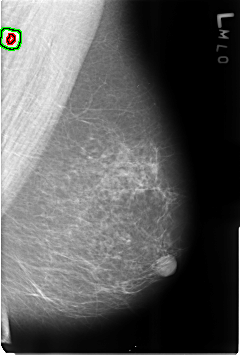

B_3180_1.LEFT_MLO

LEFT_MLO LINES 4608 PIXELS_PER_LINE 3112 BITS_PER_PIXEL 12 RESOLUTION 50 OVERLAY

FILE: B_3180_1.LEFT_MLO.OVERLAY

TOTAL_ABNORMALITIES 2

ABNORMALITY 1

LESION_TYPE CALCIFICATION TYPE LUCENT_CENTER DISTRIBUTION N/A

LESION_TYPE MASS SHAPE LYMPH_NODE MARGINS N/A

ASSESSMENT 2

SUBTLETY 5

PATHOLOGY BENIGN_WITHOUT_CALLBACK

TOTAL_OUTLINES 1

BOUNDARY

ABNORMALITY 2